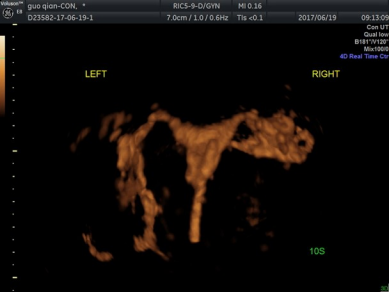

本届 “青年岗位能手”获得者——王玮:33岁,中共党员,在职博士,妇产科主治医师,助理研究员。获第九届全国优生科学大赛“优秀青年学者”奖、全国中青年围产医学论文演讲比赛全国三等奖、陕西省科技进步三等奖、陕西省超声医学会论文大赛一等奖等。擅长妊娠滋养细胞疾病超声诊断、盆底超声、子宫输卵管超声造影,胎儿畸形的产前诊断及胎儿介入超声。

王玮在“能量多普勒超声在评估妊娠滋养细胞疾病诊治”这方面的研究不仅获得了西安交通大学新医疗技术的认证,并且能够有效地协助临床评估疾病的诊疗效果及预后。她关于“早中孕期超声预测妊娠期高血压疾病”的研究也取得临床的认可,让这类妊娠急重症合并症可以早起预测、早起干预、早起诊治,减少母婴危险的发生。